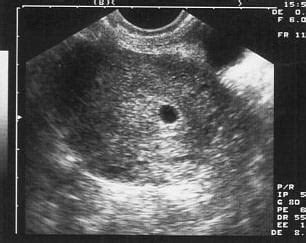

Az "üres petezsák" kifejezés arra utal, hogy az ultrahangos vizsgálat során egy petezsák látható, de embrió vagy szikhólyag nem azonosítható benne. Ennek több oka is lehet:

- Túl korai vizsgálat: Előfordulhat, hogy a vizsgálat túl korai stádiumban történik. Egyes esetekben az embrió csak a 7. vagy akár a 8. terhességi hét környékén válik láthatóvá, még akkor is, ha a petezsák már megjelent.

A tapasztalatok azt mutatják, hogy sok nőnek volt már ilyen élménye, és a terhesség később sikeresen folytatódott. Például, volt olyan eset, ahol 8 hetesen egy 29 mm-es üres petezsák látszott, de két hét múlva már volt szívhang. Más esetekben 7 hetesen 24 mm-es üres petezsákot láttak, majd két hét múlva már ott volt a baba és dobogott a szíve.

Számos női fórumon találhatunk hasonló történeteket, ahol az aggodalom végül szerencsés kimenetellel zárult. Az egyik hozzászóló például arról írt, hogy 7 hetesen még nem látták az embriót, csak a petezsákot, de 2 hét múlva már volt szívhang. Egy másik esetben 6 hetesen csak egy 7,1 mm-es petezsák látszott, és bár aggódott, végül minden rendben lett.